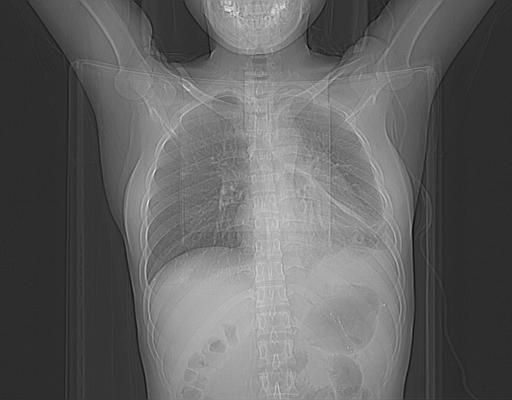

女,29岁,胸部不适,在外院胸片提示胸腔积液,到我院ct检查。

标题: CT21561:外院胸片提示胸腔积液,行CT检查。 [打印本页]